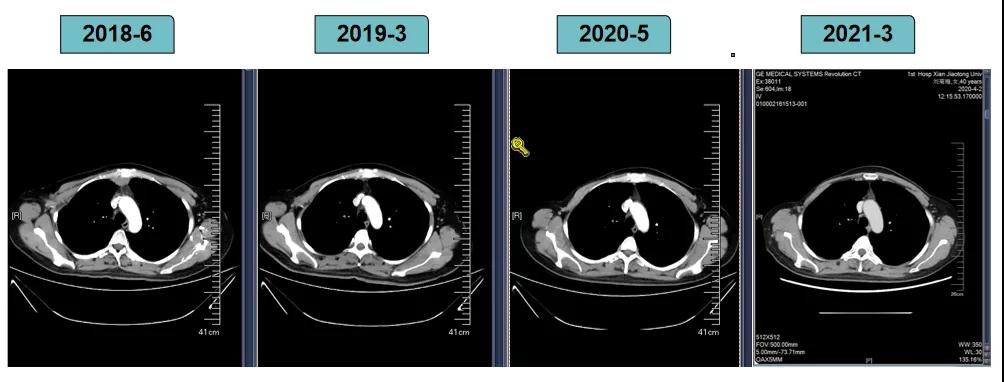

胸腹部增强CT示(2018-6-28):胸骨后占位,肝内异常强化灶,腹膜后肿大淋巴结。

2018-7-17成功入组ELAINA临床研究(试验方案编号:BO29919),IWRS分配随机号3210。于2018-7-17开始接受T-DM1 3.6mg/kg(252mg)治疗,并间断对其进行疗效评估。现阶段患者PFS达近40个月。

靶病灶:腹主动脉左侧和下腔静脉右侧淋巴结

非靶病灶:肝左叶、肝右前叶下段;纵膈胸骨后淋巴结节;前上纵膈淋巴结;腹膜后小淋巴结

影像学评估-纵膈淋巴结: